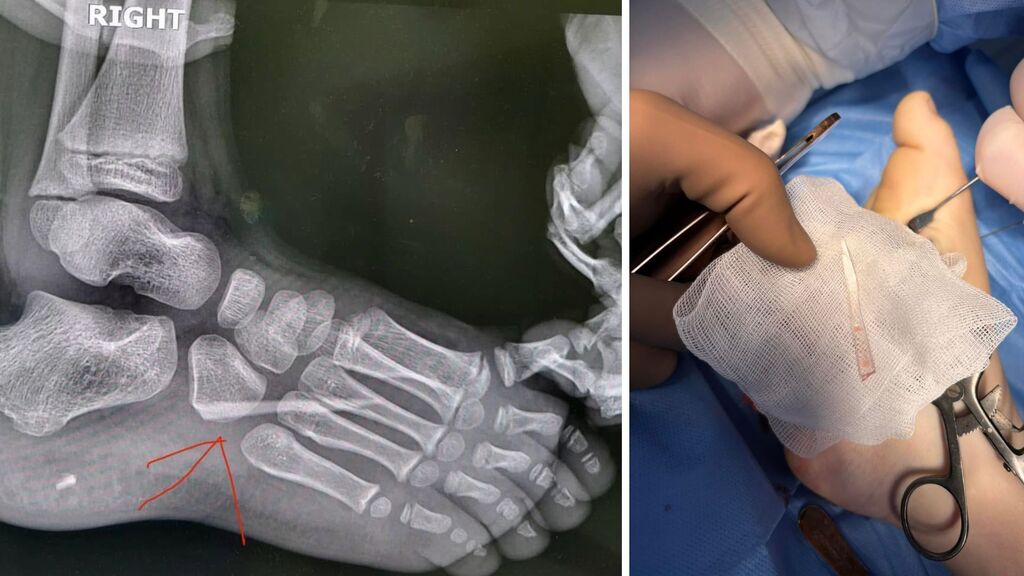

Після клінічного огляду та рентгенологічного обстеження лікарі виявили у стопі стороннє тіло — великий уламок скла. Медикам вдалося успішно провести операцію та видалити уламок без ускладнень.